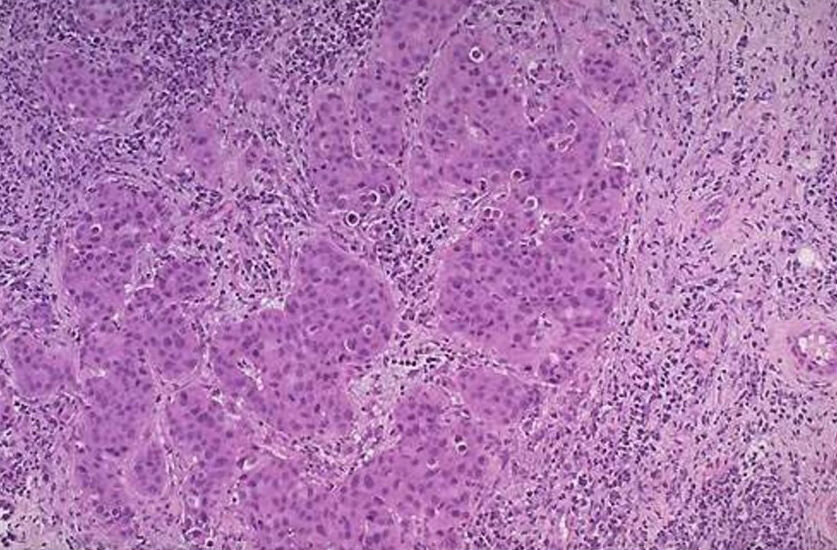

Медуллярный рак молочной желез

Медуллярная карцинома — более редкая форма ИДК, на ее долю приходится около 5% всех случаев рака молочной железы. Опухоли медуллярного рака мягкие и "мясистые".

Медуллярная карцинома обычно не растет быстро и не распространяется за пределы молочной железы, поэтому ее легче лечить, чем другие формы рака молочной железы.